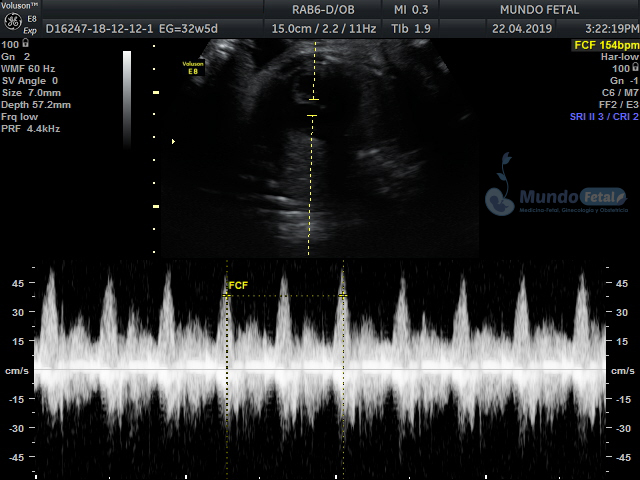

Mediante esta técnica ultrasonográfica, evaluamos en tiempo real al bebe y monitoreamos electrónicamente la frecuencia cardiaca fetal, vigilando los siguientes parámetros:

A cada parámetro se le asigna un puntaje basado en una escala del 0 al 10. Se ha propuesto que en estados fetales alterados por disminución del oxígeno se alteran los parámetros de manera que podemos predecir el estado fetal evaluando estos puntos.